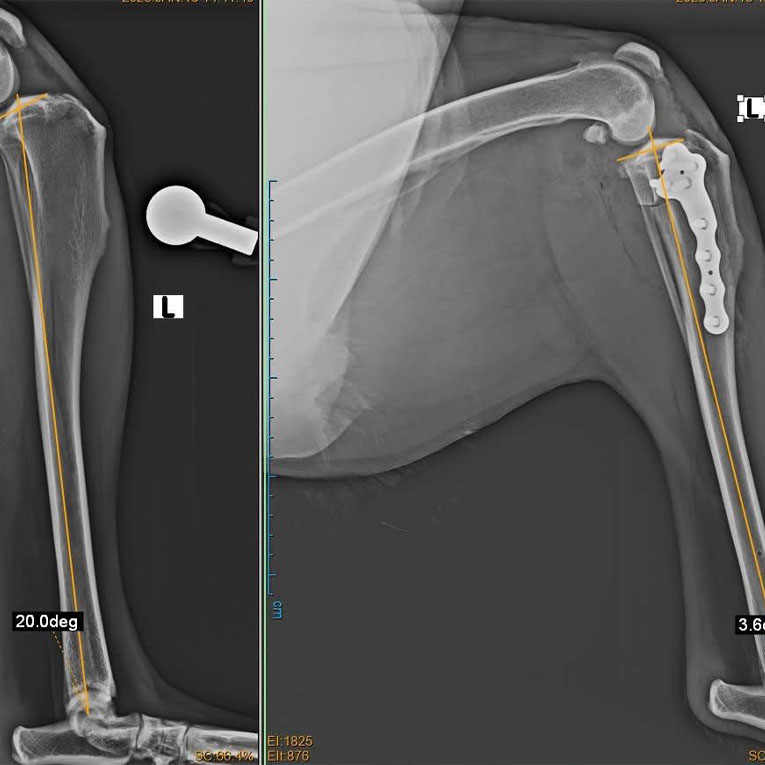

At the Veterinarium Clinic of the Agricultural University of Georgia, TPLO surgery has been successfully performed on 5 additional large-breed canine patients: 2 Caucasian Shepherd mixes, 1 German Shepherd, 1 Pointer, and 1 Cane Corso.

Surgical treatment using Tibial Plateau Leveling Osteotomy (TPLO) is considered one of the most effective and advanced approaches for managing cranial cruciate ligament rupture. Recognized internationally as the gold standard, TPLO has a high success rate of 90–95%, restores stable limb function, and significantly improves the patient’s quality of life.

At Veterinarium, surgical planning is carried out using the licensed vPOP PRO (Veterinary Preoperative Orthopaedic Planning) software by the clinic’s Head Veterinarian, Dr. Lasha-Giorgi Japaridze. This leading global platform enables precise preoperative assessment, including bone measurements, implant selection, and prediction of surgical outcomes, ensuring optimal procedural accuracy.

All five TPLO procedures were performed by Dr. Lasha-Giorgi Japaridze, who has completed advanced specialized training in TPLO surgery (Advanced TPLO – The Next Level) in Bulgaria with the support of the Agricultural University of Georgia. He holds a Master’s degree in Veterinary Medicine and is currently a PhD candidate and lecturer in surgical disciplines at the Agricultural University of Georgia.